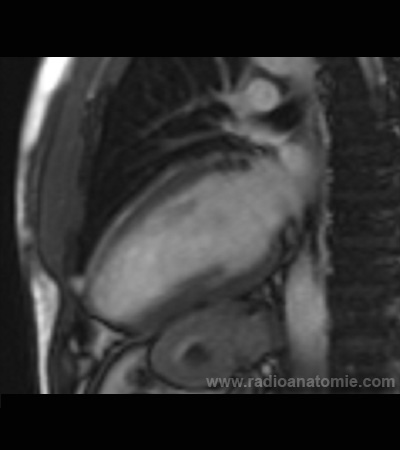

Radioanatomie et plans de coupe en IRM cardiaque

Coupe long axe 2 cavités

Ventricule gauche